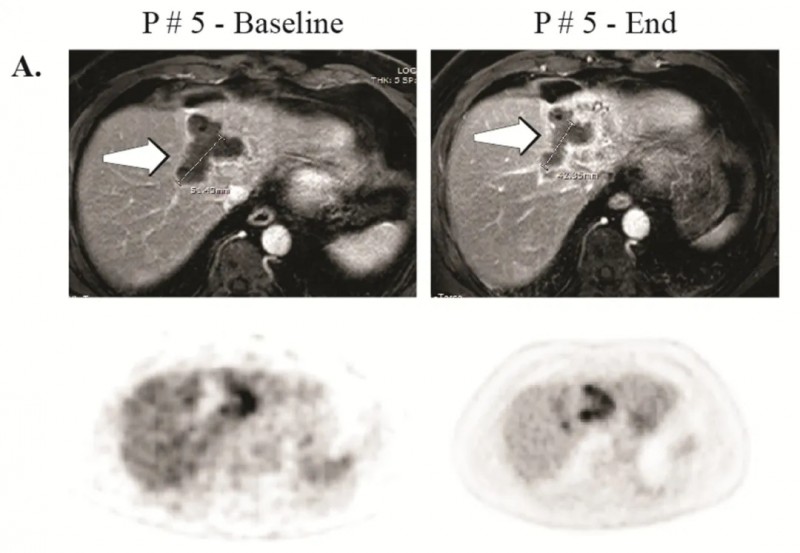

《临床癌症研究》报道的一项I期临床试验——应用CAR-T细胞肝动脉灌注治疗(HAI)CEA阳性肝转移瘤,成功验证了该疗法的可行性。